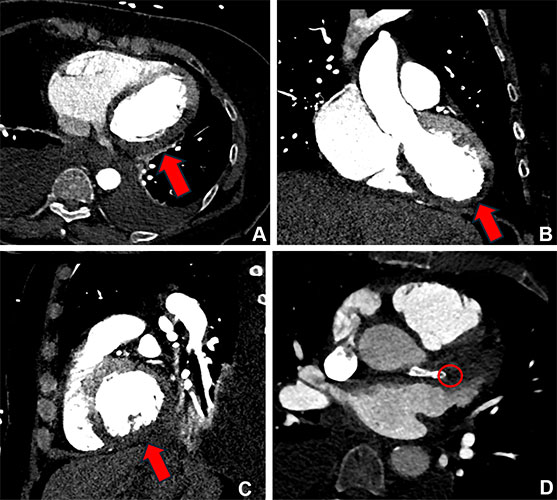

CT Angiography of Lower Extremity Aortoiliofermal Arteries

Peripheral arterial disease (PAD) of the lower extremities is a leading cause of cardiovascular illness and death. Disease severity can vary widely, from patients presenting with no symptoms to muscle pain to even limb-threatening ischemia.

CT angiography (CTA) of the aortoiliofemoral (AIF) arteries in the abdomen, pelvis and lower extremities is an essential tool for evaluating patients with PAD and lower extremity trauma.

This advanced modality offers detailed visualization of vascular anatomy, helping clinicians accurately assess blood flow, identify blockages and plan effective treatment strategies.

A recent RadioGraphics article provides a detailed overview of normal vascular anatomy, key collateral pathways and specific AIF CTA protocols for imaging PAD.

Anup S. Shetty, MD, associate professor at the Mallinckrodt Institute of Radiology at Washington University School of Medicine in St. Louis, and colleagues provide tips for reading AIF CTA exams, reporting the results and recognizing the pitfalls that can lead to misdiagnosis or diagnostic uncertainty.

“An understanding of the anatomy at hand and the clinical questions to answer, an organized and structured approach, and awareness of the spectrum of imaging findings will lead to greater success in efficiently tackling these challenging examinations to further patient care,” the authors conclude.

Read the full article, “Aortoiliofemoral Lower Extremity CT Angiography.”

Arteriovenous fistula resulting from a gunshot injury in a 27-year-old man. (A) Axial arterial phase CT image shows an irregularly shaped channel (blue arrow) between the left superficial femoral artery (white arrow) and corresponding vein (yellow arrow). (B) Axial arterial phase CT image shows abnormal asymmetric early enhancement of the left external iliac vein (yellow arrow) similar to the degree of enhancement of the left external iliac artery (white arrow), upstream from the AVF. (C) Oblique sagittal arterial phase MIP CT image shows the fistula (blue arrow) between the superficial femoral artery (white arrow) and corresponding vein (yellow arrow).